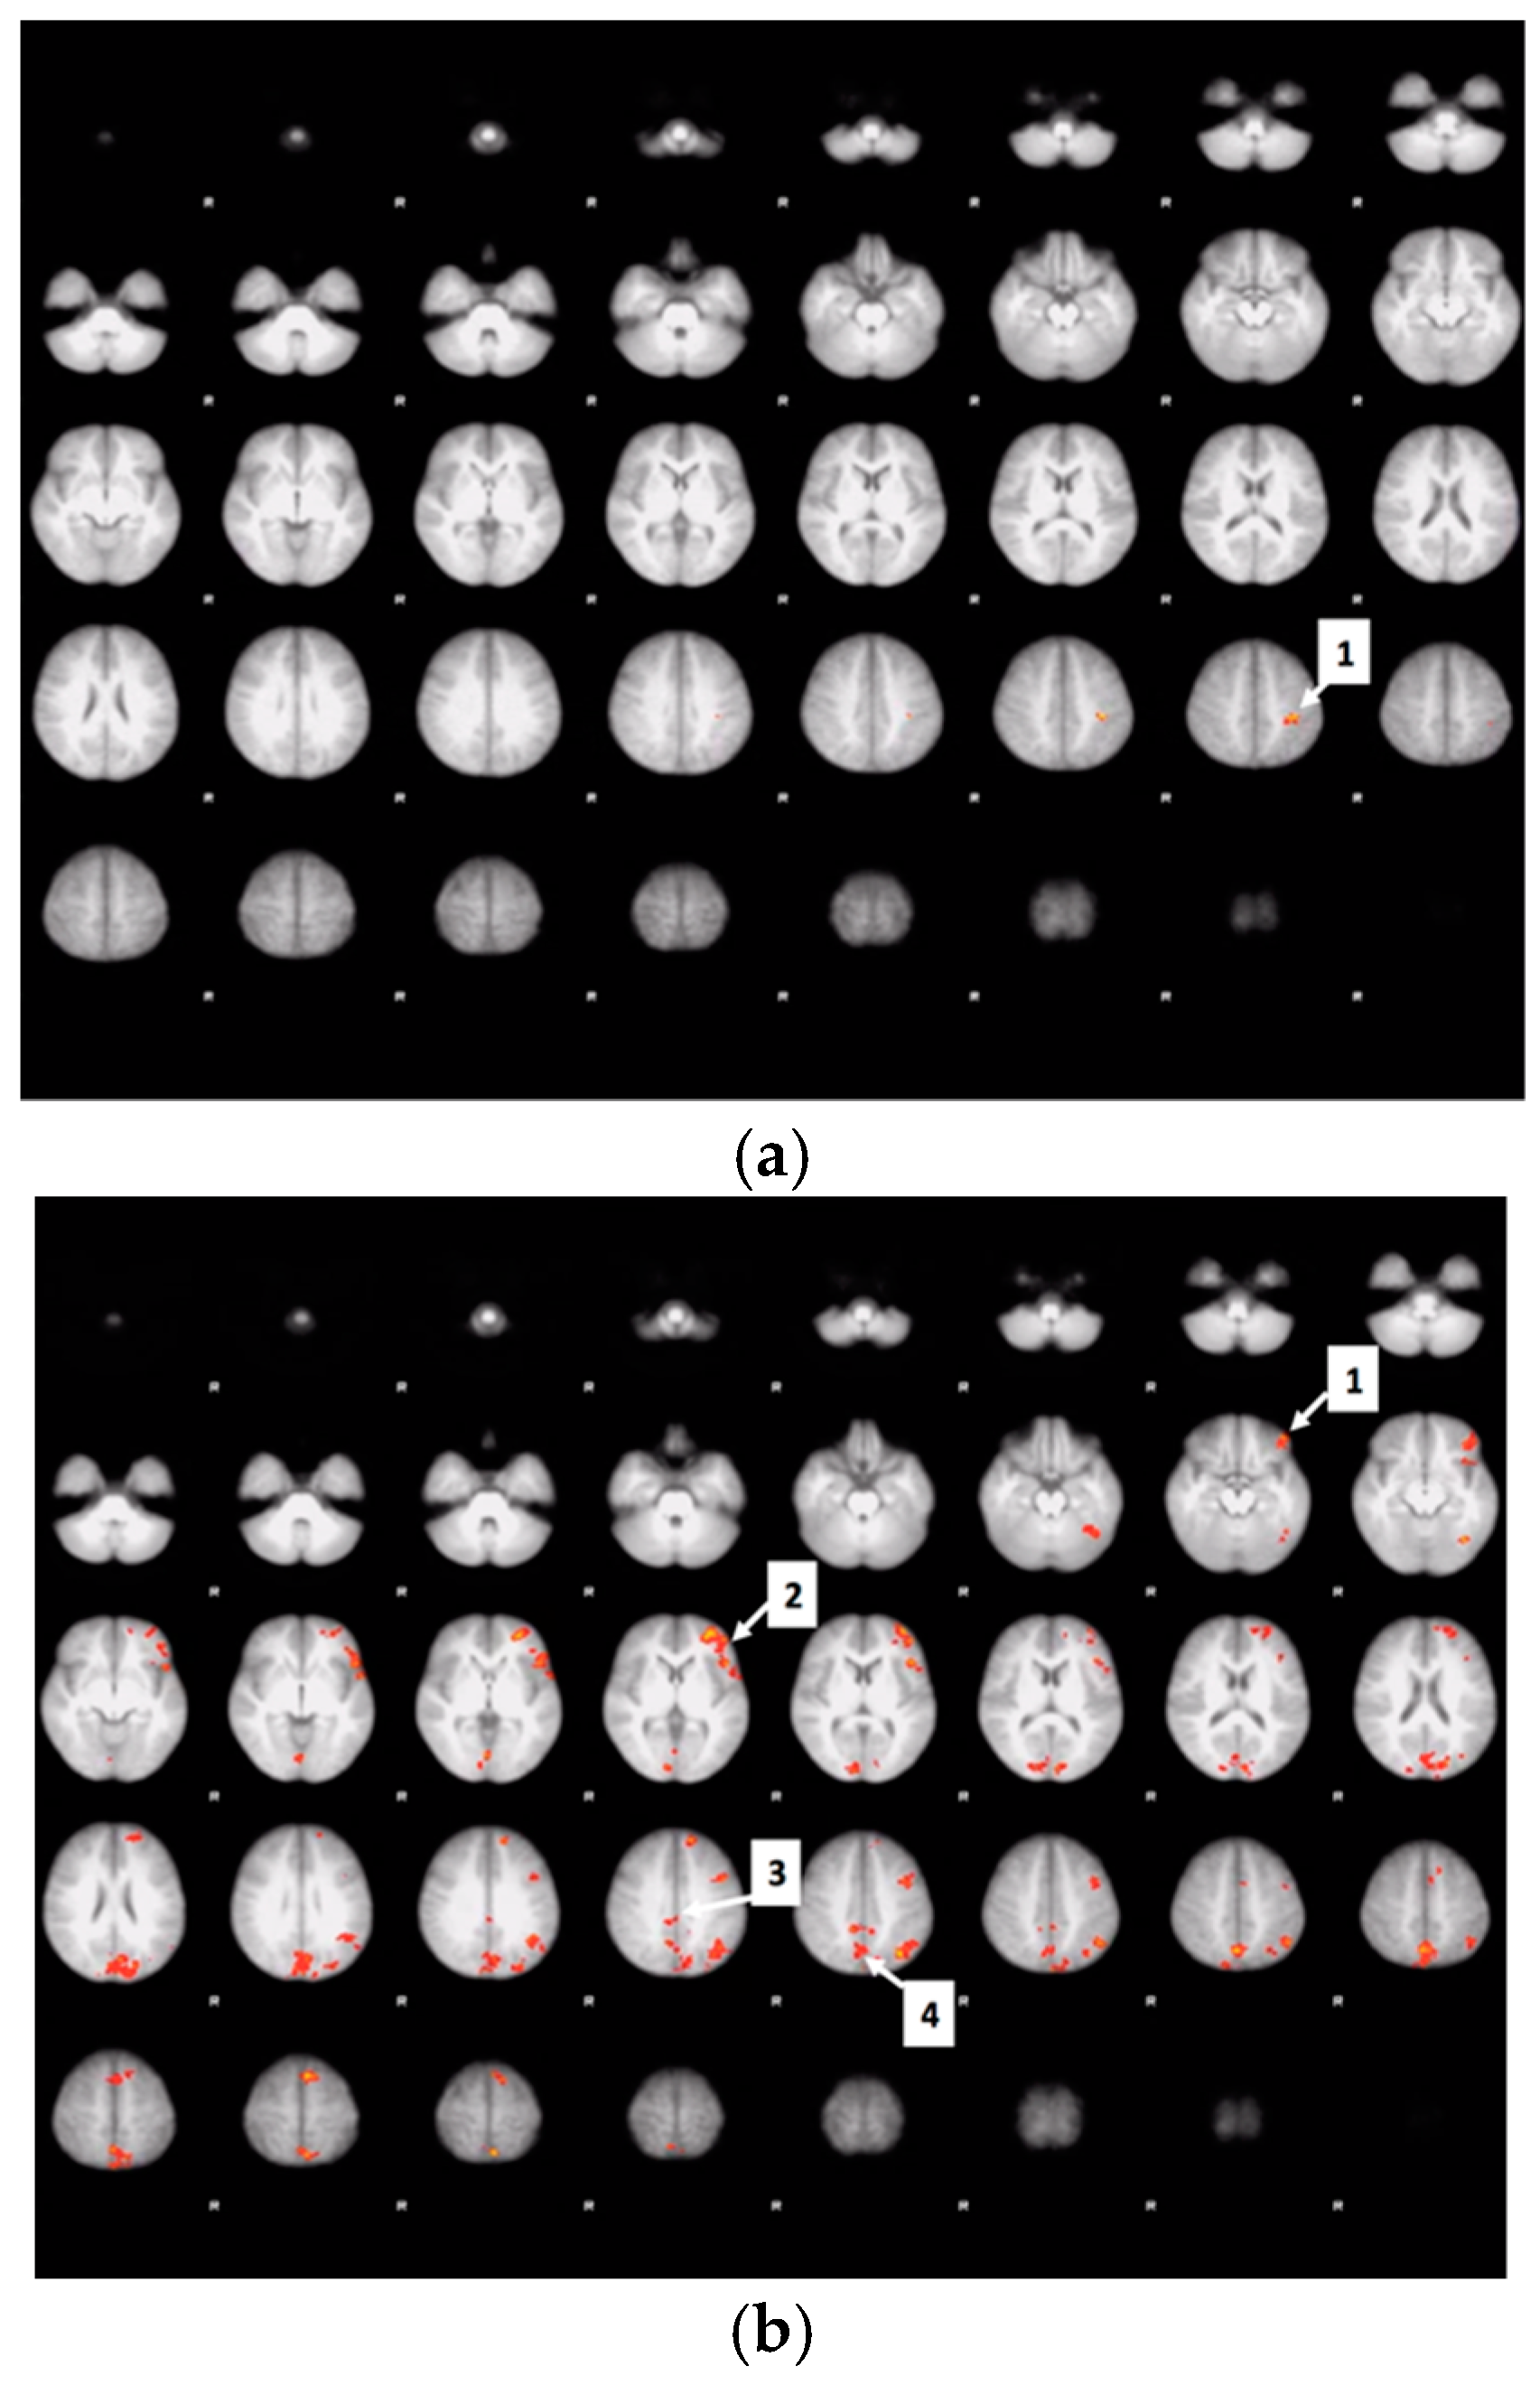

3.7. Drink Effects on Whole Brain Activity Associated with Food Valuation